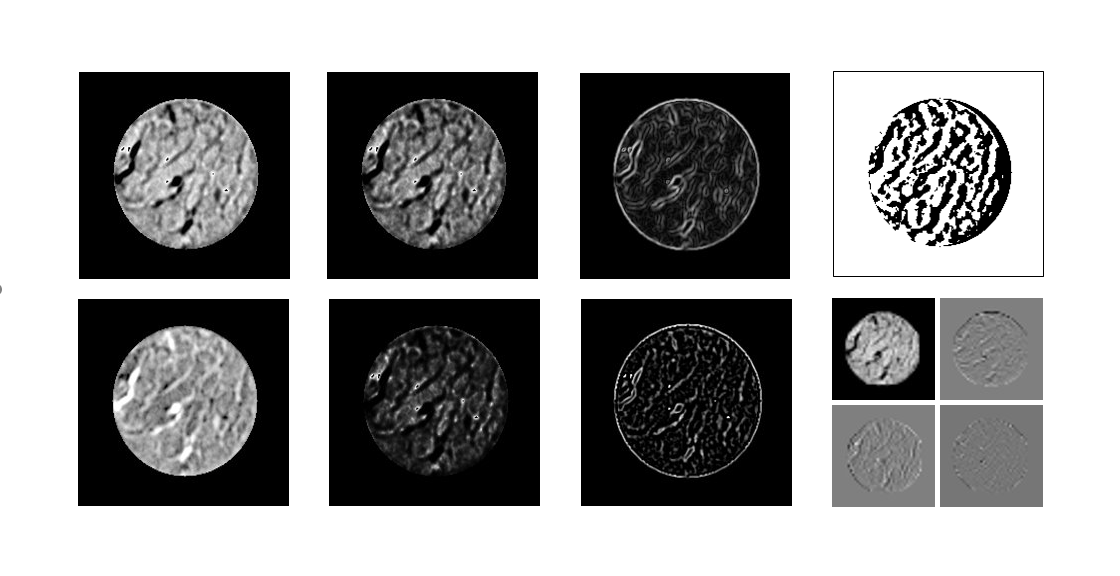

A differential phase-contrast microscope with a low-coherence light source